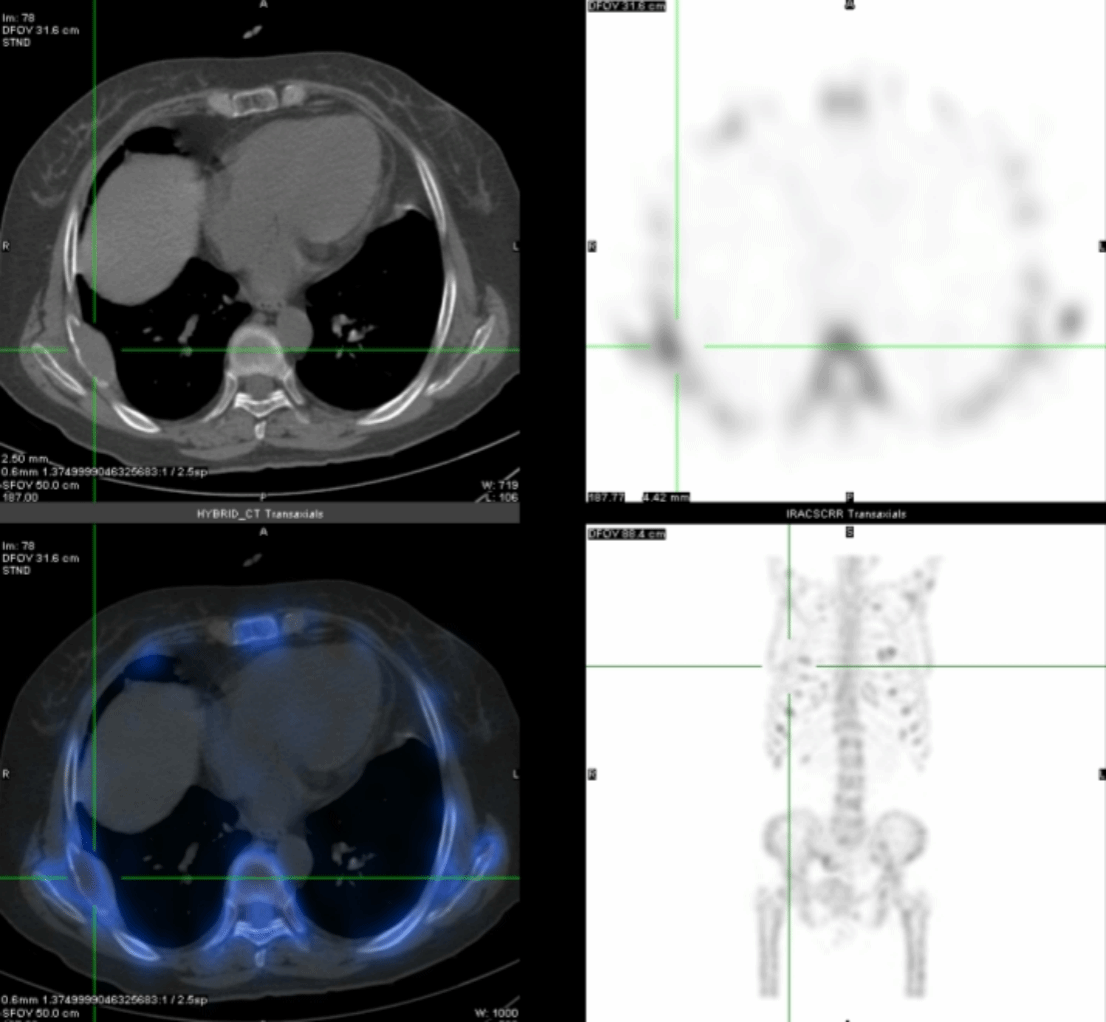

进一步的SPECT/CT断层融合显像(图2-4)显示:肋骨、肩胛骨、骶骨等灶性异常显像剂浓聚处伴骨质膨胀性骨质破坏。

通过全身显像,可以判断这些异常并非骨转移瘤所引起,而是一种代谢性骨病,结合SPECT/CT所示多发溶骨性骨质膨胀性破坏,考虑为甲状旁腺功能亢进所致代谢性骨病伴棕色瘤。为了进一步验证,段阿姨进行了血清电解质和甲状旁腺激素的测定,结果显示她的血清钙(3.14mmol/L)和甲状旁腺激素(1548pg/ml)水平明显增高,从而证实了甲状旁腺功能亢进症的诊断。段阿姨无慢性肾脏疾病、骨软化症、肠吸收不良综合征、维生素D缺乏等疾病的病史,因此诊断为原发性甲状旁腺功能亢进症。原发性甲状旁腺功能亢进症首选治疗方法为手术[1],而手术的成功主要取决于术前对功能亢进的甲状旁腺病变的精确定位,甲状旁腺显像则对识别功能亢进的甲状旁腺病变具有非常重要的意义[2]。